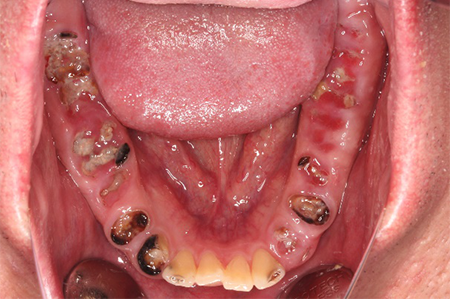

この患者様は長い事歯科医院には通っておらず、下の歯は前歯以外は全て崩壊していることが分かります。

前から見ても歯が欠けてしまい、歯茎も赤く腫れてしまっているのが分かります。

一般的には入れ歯が妥当かと思われますが、患者様は33歳、まだまだ人生は長いです。

奥歯がないと前歯でしか噛めなくなってしまい、残っている前歯もいずれダメになってしまいます。

また、奥歯がなくなってからの期間が長かったため、入れ歯が入るスペースが奥にないのが分かります。

様々なことを鑑み、患者様とも何度も話し合いを行い、下の奥歯には必要最低限のインプラントを、他の歯も外科処置を施しなるべく歯を抜かない方法を取りました。

最終的に抜歯した本数は下の歯5本。上の歯に関しては全て残すことが出来ました。

奥歯があることで前歯の負担を減らし、前歯を失うリスクを下げることが出来ます。